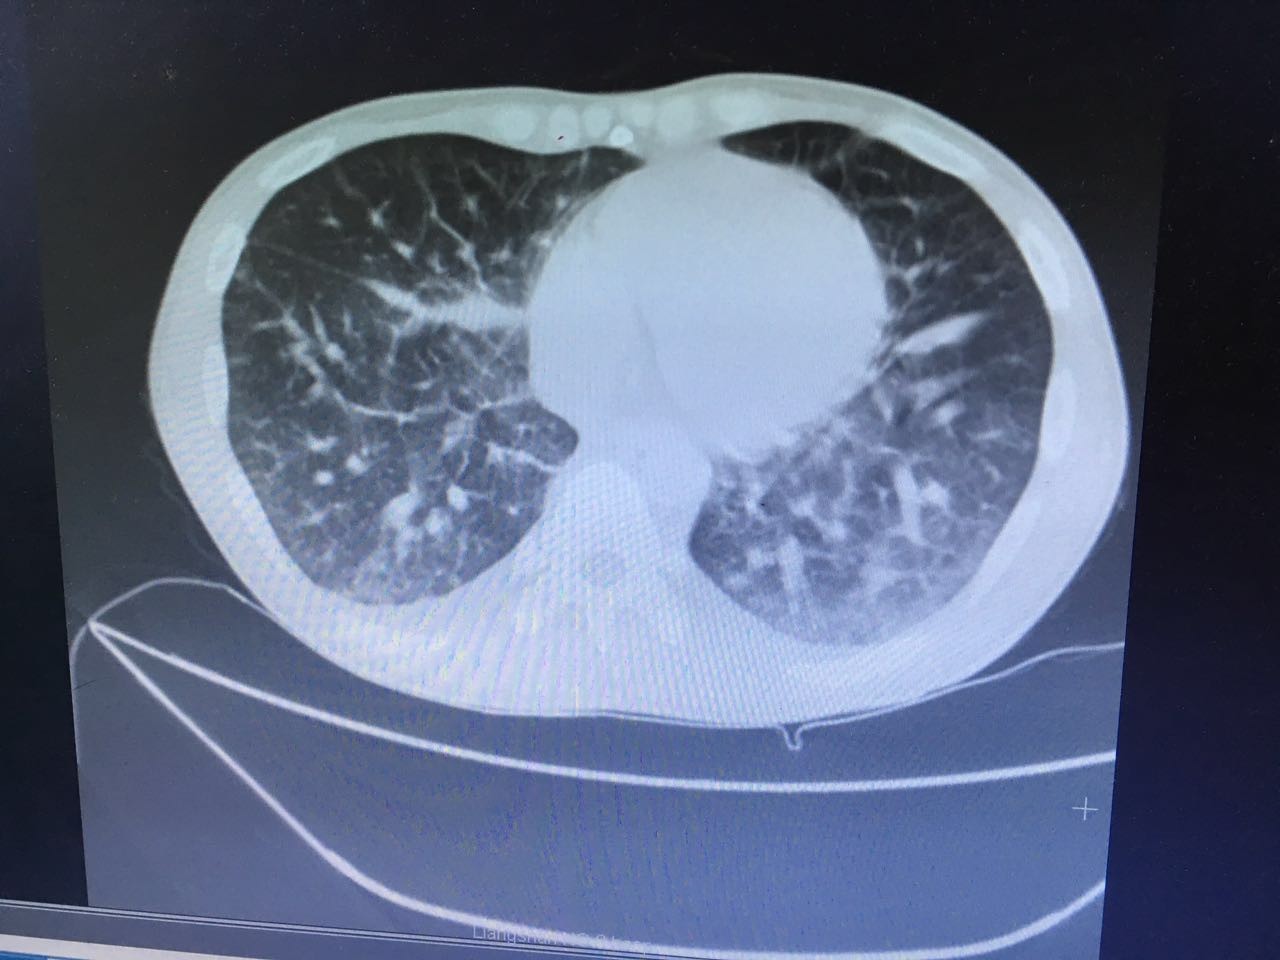

第二天,肺部CT做下来,我们傻了,和胸片差别太大了!从中下肺开始,那是大片的阴影啊!CT提示为间质性肺炎,找放射科主任读片,认为不符合肺结核、肺癌的表现(图1-3.)马上再回到病床前再次确认——没有吸烟史、没有慢性咳嗽史、没有咯血、没有盗汗史。再查体:浅表淋巴结确实不肿大,双肺呼吸音可以算略粗糙也可以算清晰。——这么这么静默的肺部体征,这么这么差的影像学结果,马上补查肿瘤标志物和自身免疫全套吧!

图1

图2

图3